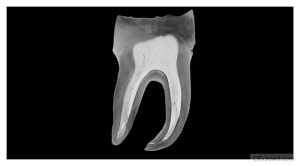

Join us for the Advances in Dentistry - Implantology, Digital Dentistry, Robotics and AI-Driven Dental Congress at Tufts University, where dental professionals will explore cutting-edge innovations and technologies.